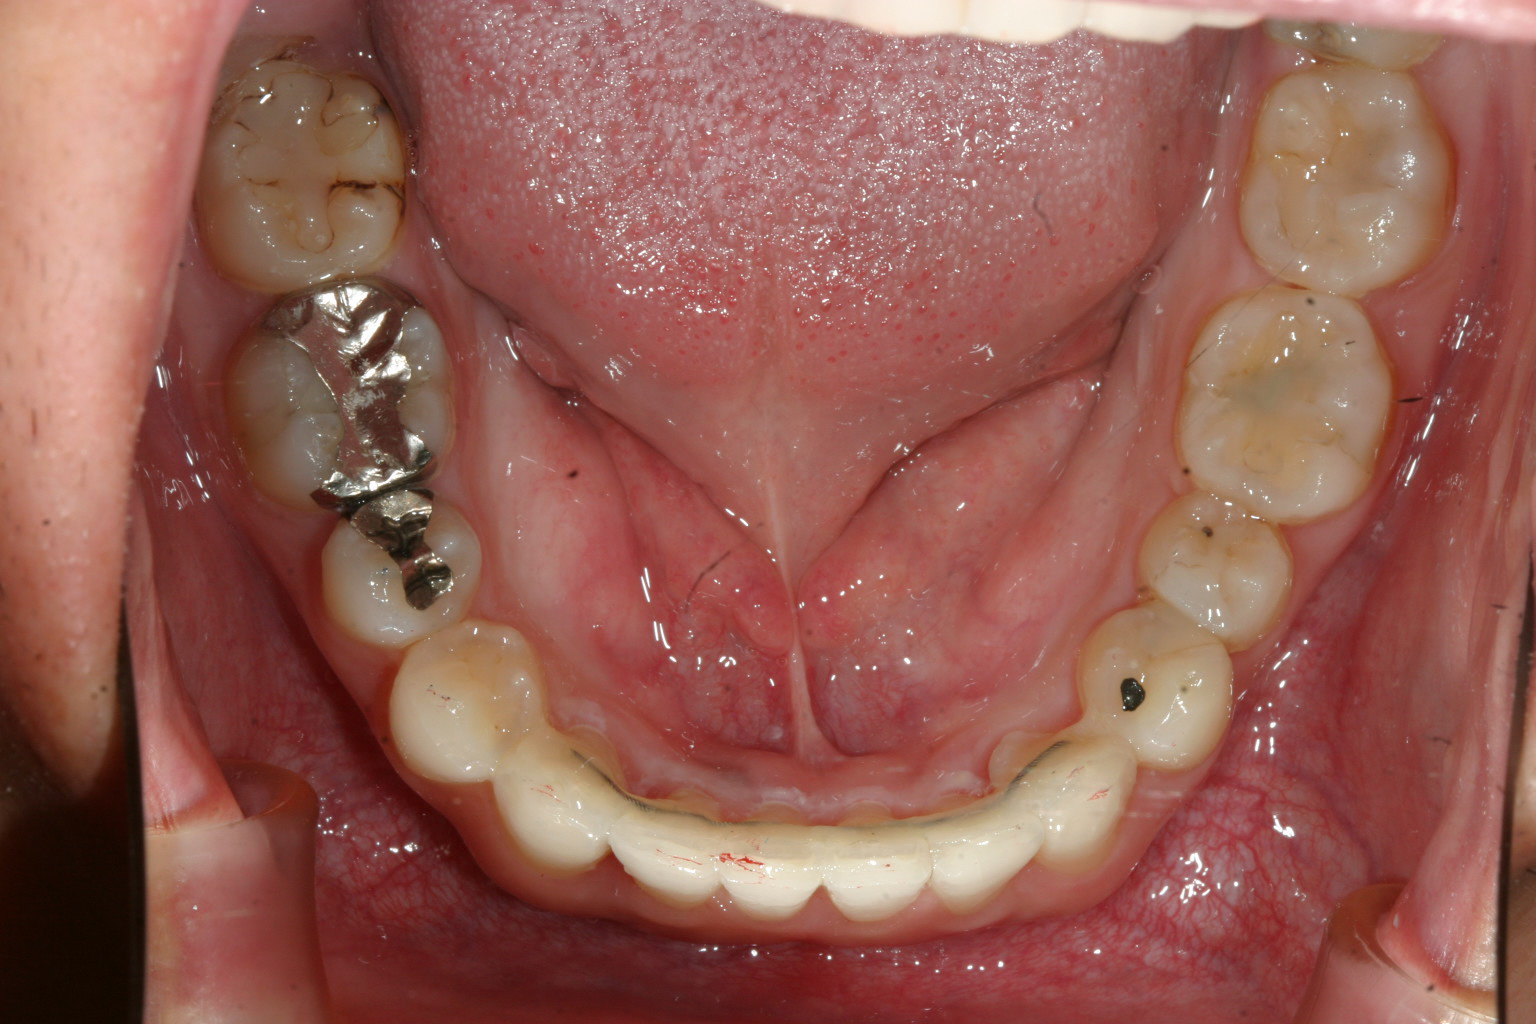

下顎も依然と比べると見違える程綺麗になりました。

下の歯が綺麗に見えますでしょ? オーバーバイト(過蓋咬合)も改善されています。

インビザラインによる叢生と過蓋咬合の改善例です。